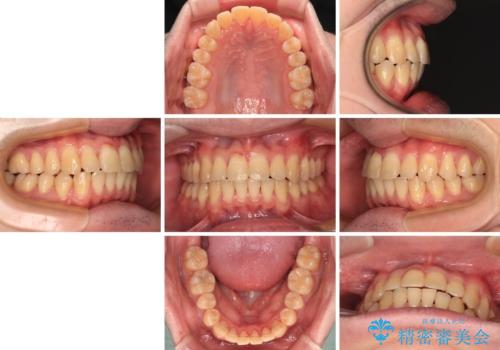

【モニター】前歯のデコボコとクロスバイト ワイヤー矯正で短期間に仕上げる

- 1年1ヶ月

- 前歯のデコボコとクロスバイトを気にして来院された患者様です。

インビザラインでもワイヤー装置でも矯正治療は可能でしたが、煩わしい自己管理なしに短期間で治療を行いたいとのことで、目立たないワイヤー装置にて治療を行うこととしました。